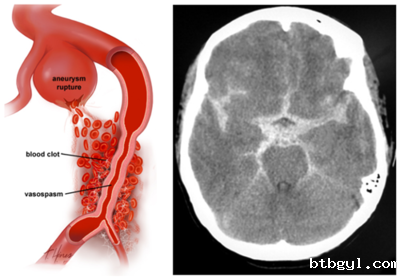

颅内动脉瘤是啥? 简单来说,就是脑动脉的某一段像吹气球一样鼓起来了。它通常长在血管分叉的地方,平时可能没啥感觉,但一旦“爆炸”(破裂),就会引发脑出血,后果非常严重! 谁更容易“中招”? 全球约3%-5%的人有颅内动脉瘤。 女性比男性更容易得(姐妹们要当心!)。 高发人群:高血压患者、长期吸烟的人、有家族病史的人,以及多囊肾患者风险更高。 破裂了会怎样? 每年1%-2%的动脉瘤会破裂,破裂后死亡率高达40%-50%!破裂时,人会突然感到“这辈子最剧烈的头痛”,还可能伴随恶心、呕吐、脖子僵硬,甚至昏迷或猝死。即使抢救及时,也可能留下神经功能障碍,比如手脚不灵活、说话不清楚等。 高医生遇到的真实故事 45岁的王女士,长期吸烟还有高血压。某天上厕所时,她突然感到一阵剧烈的头痛,接着恶心、呕吐,差点晕倒。送到医院后,医生发现她的颅内动脉瘤破裂了,引发了脑出血。经过紧急手术,她幸运地活了下来,但留下了部分后遗症。 这个案例告诉我们:早发现、早治疗,真的能救命! 没破裂时会有啥症状? 大多数时候没感觉,就像一颗“定时炸弹”,悄无声息。少数人可能会感到头痛、视力模糊、眼皮下垂或看东西重影。如果出现这些症状,别拖,赶紧去医院检查! 怎么检查? CT、CTA、MRI/MRA:这些影像学检查可以帮医生看清楚动脉瘤的位置和大小。 怎么治? 开颅夹闭术:打开脑袋,用夹子夹住动脉瘤的根部,防止它破裂。 血管内介入治疗:通过血管把弹簧圈塞进动脉瘤里,让它慢慢闭合。 具体用哪种方法,得听医生的建议。 怎么预防? 控制血压:高血压是动脉瘤的“好朋友”,一定要把血压控制在正常范围。 戒烟:吸烟会大大增加动脉瘤的风险,赶紧戒了吧! 健康饮食:少吃油腻,多吃蔬菜水果,保护血管健康。 定期体检:尤其是高危人群,做个脑部检查,心里更有底。